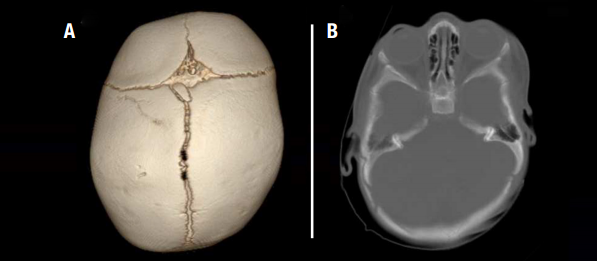

Sometimes, craniosynostosis can be diagnosed with an office examination alone. Often, imaging will be used to more closely examine the cranial sutures and confirm the diagnosis. Here at Nationwide Children’s we use a special CT scan that provides 3D views of the skull using an ultra-low radiation dose equal to that of only a few regular x-rays.